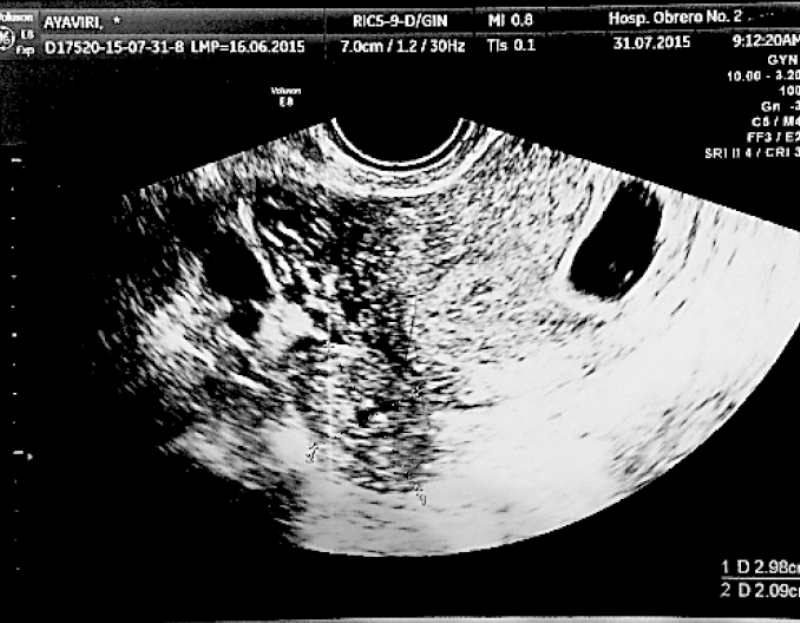

It was concluded that this was a heterotopic pregnancy: an intrauterine pregnancy of 6.4 weeks with confirmed vitality and a right tubal ectopic pregnancy ( Figure 2).